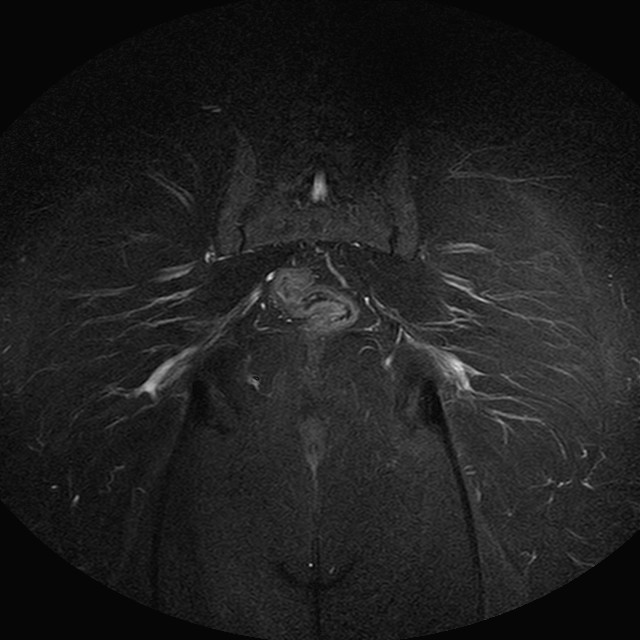

eSTIR

Evidenti e simmetriche alterazioni osteofitosiche in regione coxo femorale con riduzione delle rime articolari. Degenerazione completa del cercine glenoideo. Non attuali segni di versamento articolare. Non segni di edema osseo che escludono attuale algodistrofia od osteonecrosi. Lieve e simmetrica riduzione del trofismo della muscolatura glutea.